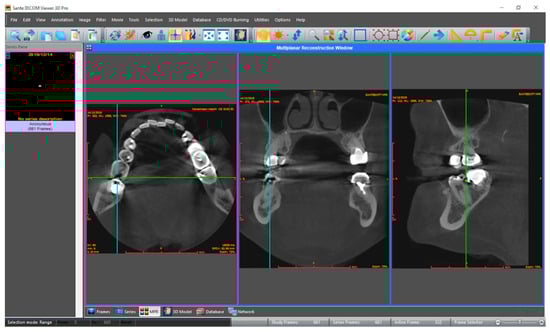

Three observers in dentomaxillofacial radiology evaluated CBCT volumes for dental caries signs, without and with the Diagnocat system. An online conference was conducted prior to evaluations for the calibration of the observers with different levels of experience. The results of aided and unaided evaluations were collected in a template document to ensure standardization among observers. The template with dedicated columns for ‘tooth condition’, ‘mesial surface’, and ‘distal surface’ for each tooth was prepared to collect the responses in an organized manner. Tooth conditions were saved as ‘intact’, ‘missing’, ‘restorated’, ‘support’ and ‘excluded’. Mesial and distal surfaces of the tooth were scored by independent observers separately for the presence of caries on a five-point confidence scale: (1) caries definitely absent, (2) caries probably absent, (3) unsure, (4) caries probably present, and (5) caries definitely present. Primarily, the dataset was imported to Sante DICOM Viewer Pro (Santesoft Ltd., Nicosia, Cyprus) by each observer independently (version 11.6.2 for Windows, 2.0.1 for macOS), and unaided evaluations were performed without any restriction and saved (Figure 1). After a month-long time interval, the dataset was uploaded to the Diagnocat system, and CBCT volumes were analyzed to generate a radiological report. Observers were granted access to the web-based system (Figure 2) to re-evaluate the samples with the aid of the Diagnocat system, and the results were saved using new duplicates of the template.

Figure 2.

Interface for aided evaluation (Diagnocat). On the left side, at the top, the synthetic–panoramic image produced from the CBCT volume is provided for an overall view, while underneath, there is a dental chart that provides information about the condition of each tooth. The colors of white and purple represent a healthy and treated tooth, while the red means an unhealthy or missing tooth. On the right, the predictions of the system for the relevant tooth are provided by image slices in different axes.